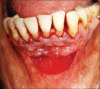

Gingival recession is defined as the apical migration of the gingival margin with exposure of root surfaces. The etiology of the condition is multifactorial. Given the high rate of gingival recession defects among the general population, it is imperative that dental practitioners have an understanding of the etiology, complications and management of the condition. A recent innovation in dentistry is the preparation and use of platelet-rich fibrin (PRF) for recession defects. The article presents a case report, which highlights the use of lateral sliding bridge flap along with PRF in a collagen membrane carrier (guided tissue regeneration) for the treatment of multiple recession defects.